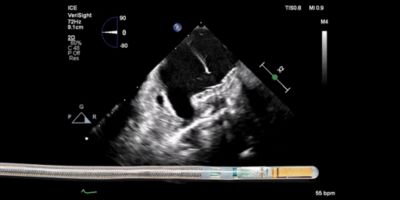

One Platform. Multiple Possibilities. The Future of ICE in EP.

Join the engaging discussion on the evolving role of advanced ICE imaging in electrophysiology. Discover the impact of ICE on workflows and patient care, including concomitant LAAO and ablation procedures, and go beyond conventional 2D ICE with new solutions, all on one platform.